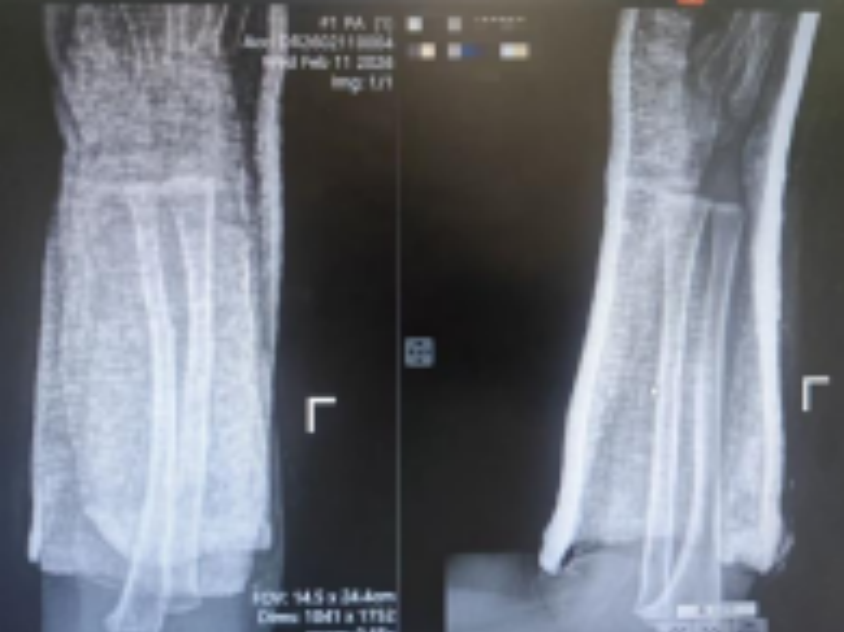

3岁的小阳阳(化名)在玩耍时不慎摔倒,当即哭闹不止,左前臂迅速肿胀变形,家长紧急将其送往西安市红会医院。影像检查提示:尺桡骨双骨折,骨折端移位明显,伴成角畸形——这类损伤在常规诊疗路径中,多建议手术切开复位内固定。

术后复查X线片显示,骨折端对位对线极佳,成角畸形完全纠正,尺桡骨恢复了正常的生理弧度。